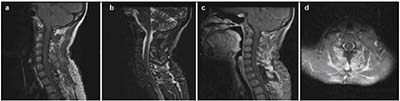

20171023160923  Figure 2 Post-operative magnetic resonance image; no recurrence of the solid tumor is evident.